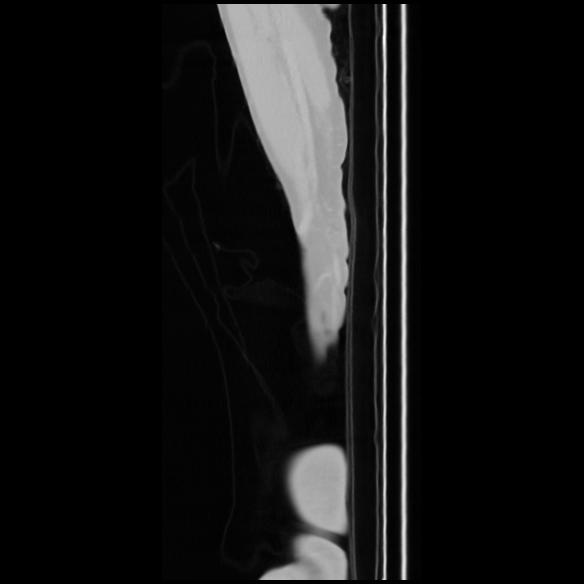

7 CUERPO,CE,Sagittal,3.000,CUERPO,Sagittal,